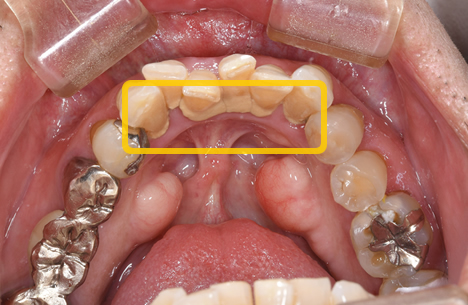

歯周病治療による改善例